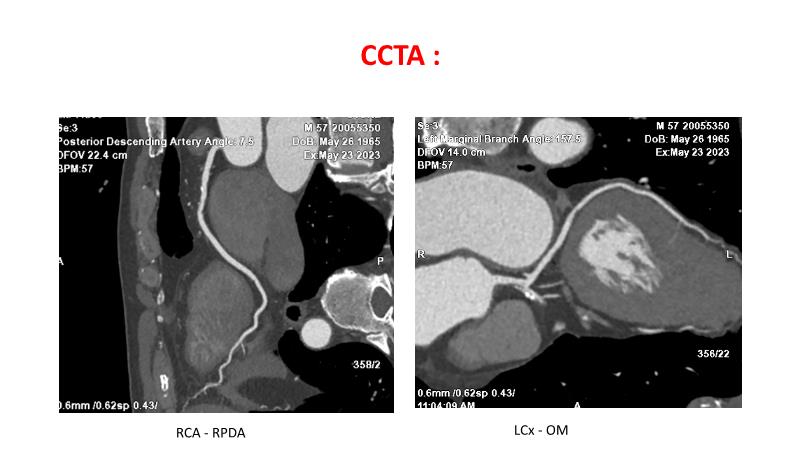

• To understand why the use of IVUS imaging is different from seeing with experienced eyes to achieve improved left main bifurcation outcome